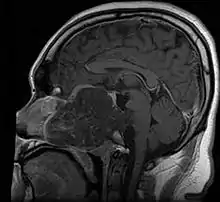

- Skull base:

- May be intracranial or extracranial, with mass effect symptoms depending on location

- Headaches and/or facial pain are common

- Pituitary insufficiency, hemianopsia/diplopia, cranial nerve deficits, nasal stuffiness.

- Maximal resection followed by proton beam irradiation.

- Overall survival is dependent upon local control of disease. Prognostic factor for local control of disease is amount of residual tumor after original surgery (<25cc residual tumor is better).

- Clear margins are achieved in <50% of skull base chordomas.

- Doses of 70 CGE necessary for control of residual disease.